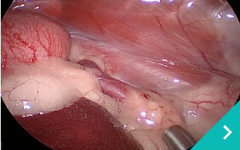

腹腔鏡手術は、この開腹手術の課題である患者さんの負担を軽減させるため、小さな傷口3つほどをあけ、胃や腸がある腹腔にCO2ガスを注入して膨らませてから内視鏡カメラやメスなどを挿入して手術する方法です。

ミニマム創内視鏡下手術は腹腔鏡だけでは対処ができないような手術の際に、お腹にラッププロテクターという器具を設置して行う腹腔鏡と開腹手術を組み合わせた手術です。